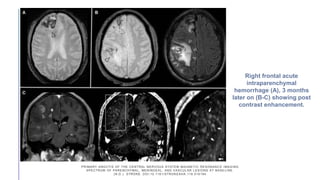

Right frontal acute

intraparenchymal

hemorrhage (A), 3 months

later on (B-C) showing post

contrast enhancement.